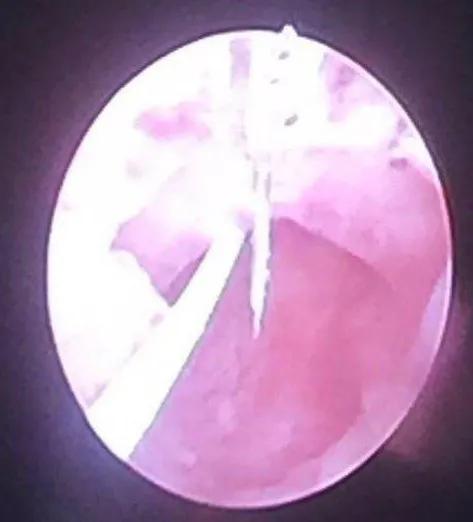

此次术中发现球部尿道前壁狭窄呈穹顶状,右侧壁狭窄呈切线状,致使F16探子都不能插入,8点位还有一个0.5厘米肉芽,也影响排尿。手术用F20中号尿道内切开镜、直角针状电极反推纵行切开12点位,镜子进入膀胱,观察尿道全程,顺行切开8点位(切线部位)。换F24大号尿道内切开镜,加深上述两条纵沟,琴弦状电极切除肉芽和7-8点位隆起的疤痕,其它尿道壁疤痕保留。F27探子顺利无阻力通过,留置F22导尿管顺利,准备1个月拔管,康复治疗一个疗程,预防粘膜粘连,扩张尿道4次左右即可治愈。

狭窄切开后发现外括约肌正常